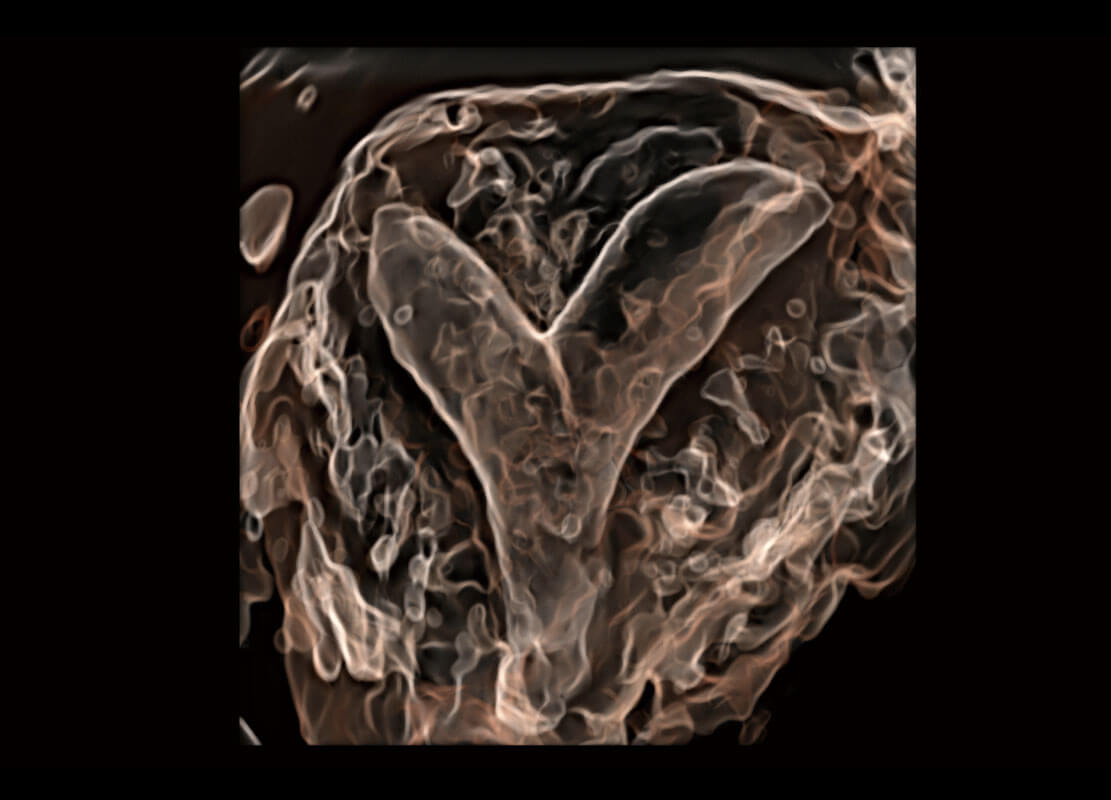

• 腔内三维-宫内节育器

• 腔内三维-光影成像

• 光影成像-孕囊